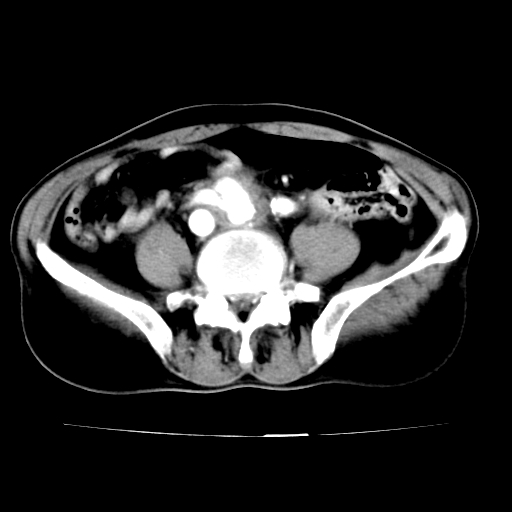

腹总动脉瘤伴附壁血栓形成累及髂总动脉

腹总动脉瘤伴附壁血栓形成累积髂总动脉 支持

腹主动脉分叉处真性动脉瘤,附壁血栓形成。

各位老师注意到下腔静脉的充盈缺损了吗?注意到动静脉漏了吗?

腹总动脉瘤伴附壁血栓形成累及髂总动脉,看起来好像有动静脉瘘,但我认为是扫描时象造成的假象。

当时是扫描的标准动脉期,可是下腔静脉与腹主动脉同步强化且幅度一致。所以我想动静脉瘘是存在的。